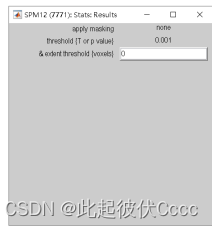

4.点击Done,之后按下图进行选择

5.出现结果